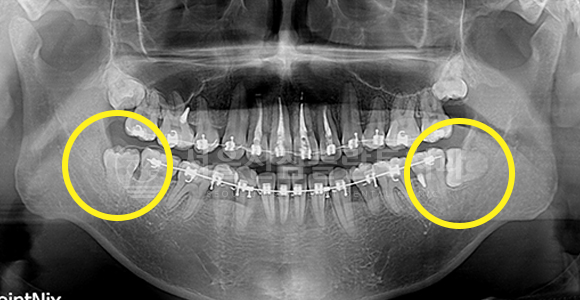

바르게 맹출된 사랑니 발치 + 매복 사랑니 발치

AFTER

사랑니가 바르고 정상적으로 맹출 되어도 구강 관리가 어려워 충치 이환도가 높아짐으로 예방적으로 발치하는 것을 추천해 드립니다.